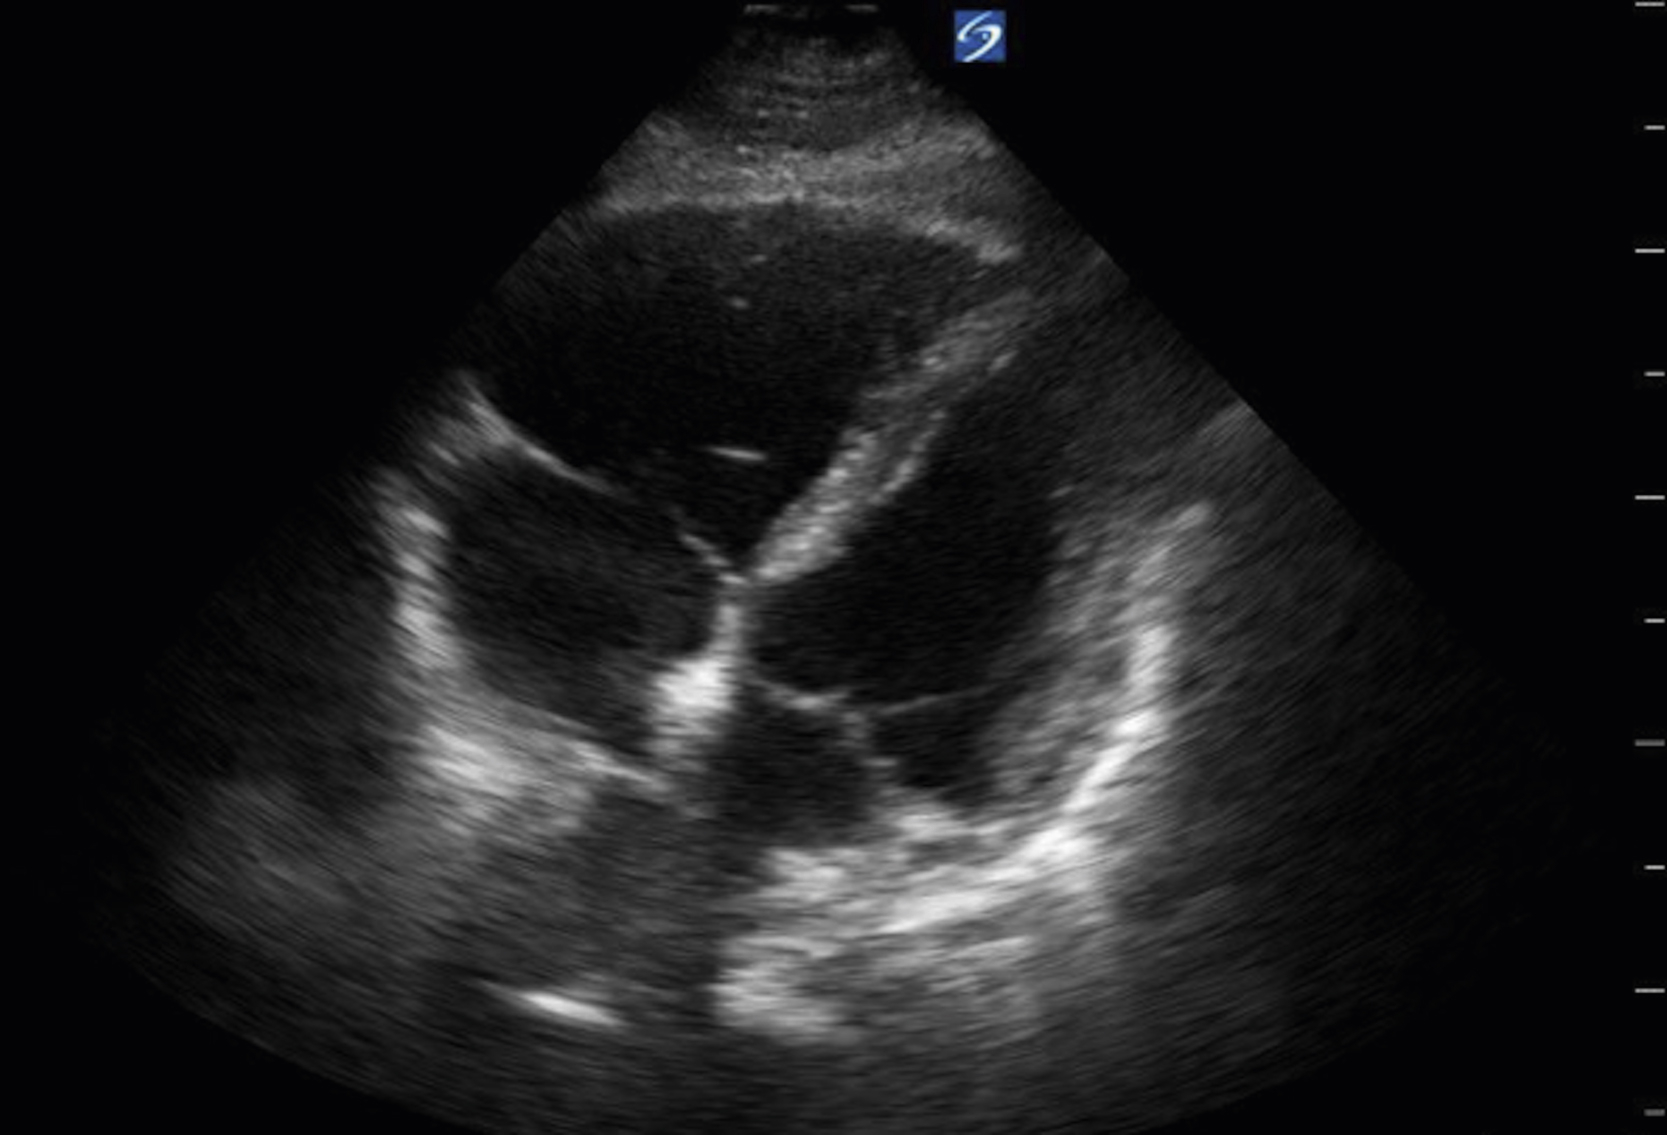

Image Acquisition

Cardiac US is performed through the transthoracic and transabdominal windows with the use of small curvilinear or phased array transducers. Typical views include the subcostal four-chamber view (subxiphoid), parasternal long-axis view ( Fig. e3.10 ; see Video e3.4 ), parasternal short-axis view, and apical four-chamber view. The subcostal four-chamber view, as in the FAST, is ideal for assessment of pericardial effusion and useful during cardiac arrest because it does not interfere with chest compressions. The long-axis subcostal view highlights the inferior vena cava (IVC) and can indicate volume status. The parasternal views are excellent windows for LV assessment. The apical four-chamber view is ideal for comparison of RV and LV sizes and function. Several US protocols have been developed to evaluate undifferentiated hypotension and can be used to narrow the differential diagnosis.

Fig. e3.10

Normal parasternal long-axis view of the heart.